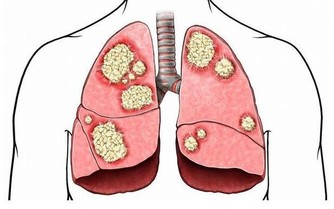

研究顯示,全球每年新發胃癌有40%以上發生在中國,而且85%以上的胃癌患者被確診時已經到了中晚期,其五年生存率迅速將到20%以下。

人們常說“人食五穀雜糧,孰能無疾”,而飲食入口,首先影響的就是胃。而且胃癌,大多是“拖”出來的!因為胃癌早期具有隱蔽性,它之所以難發現,是因為它跟普通胃病症狀很相似,而胃病又太過普遍,所以即使出現也被一拖再拖,最終到了晚期。